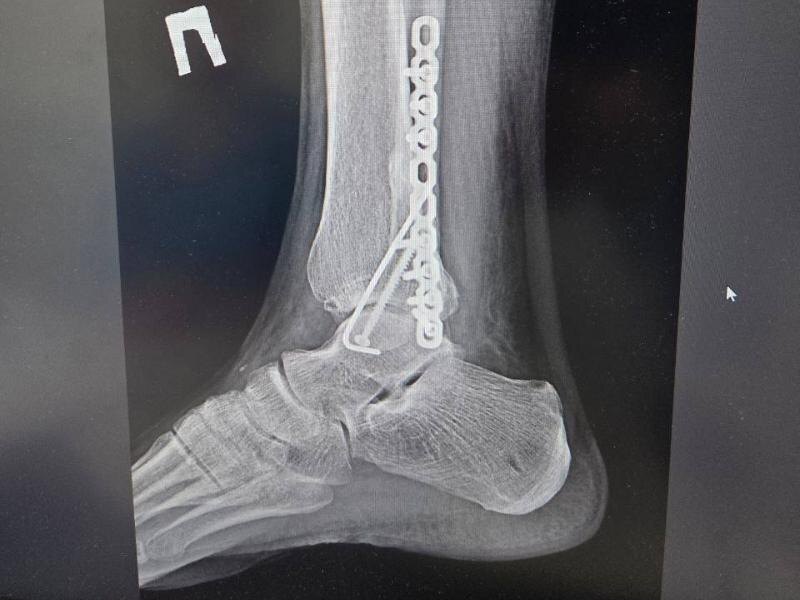

В редакцию «Блокнота» обратился воронежец Сергей, ставший участником ДТП. Еще в апреле 2025 года на территории Коминтерновского кладбища ему на ногу наехал автомобиль. В момент ДТП Сергей, работавший водителем мусоровоза, стоял возле своего грузовика. Итогом аварии стал перелом у пострадавшего двух лодыжек со смещением, вывих ступни и гематомы мягких тканей.

Снимок ноги пострадавшего